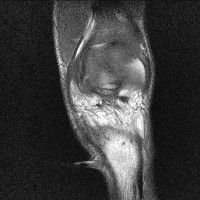

무릎 mri 간단히 봐주실 수 있으시나요 ㅠㅠ

안녕하세요 8년전 십자인대 수술하고 최근 무리한 운동에 무릎 불편감이 생겨서

mri 찍었습니다.

진단결과는 첫 찍은 병원에서 활액막염 이라는 진단을 받았습니다. 혹시 봐주실 수 있으실까요?

올라온 MRI가 단편적이라서 정확한 진단에 어려움이 있지만 십자인대에는 큰 이상이 있지는 않은것 같으며, 무릎관절내 물이 있는 것으로 보아 활액막염의 진단이 맞을 것 같습니다.

하지만 단편적인 영상이기 때문에 촬영병원에서 정확한 판독지 등을 받으시는 것이 좋겠습니다.